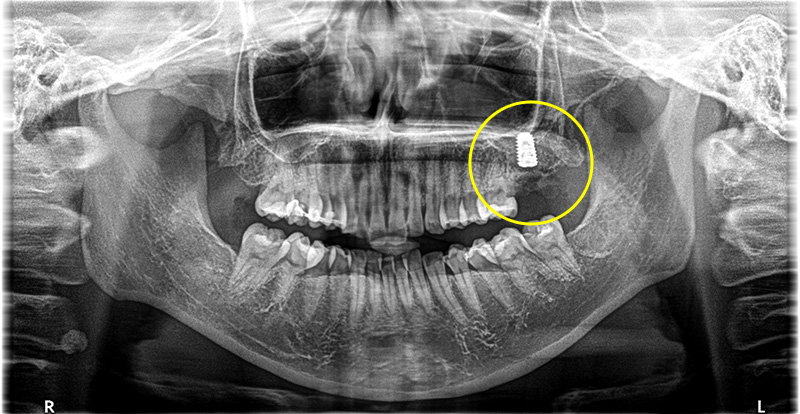

左上一番奥の歯が根破折で抜歯をインプラントで修復した症例

こちらの患者さまは、左上一番奥の歯が噛むと痛いとの主訴で来院されました。

レントゲンでの検査の結果左上7番目の歯の根が折れてしまっていることが分かりました。

根破折につき保存不可、抜歯、インプラントでの治療を行うことになりました。

インプラント治療の実施

根破折により膿が大きく、骨欠損の範囲が大きかったため、インプラントの持ちを良くするため骨造成も同時に行っています。